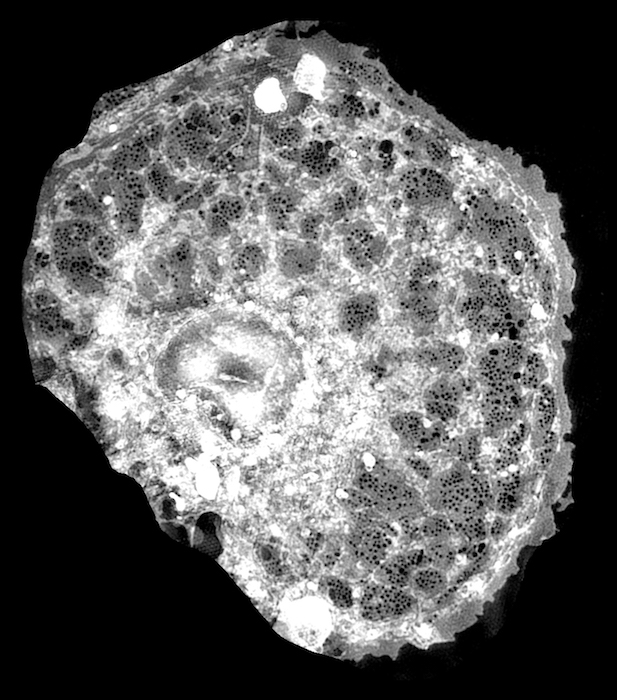

Image of a single endothelial cell from the liver obtained with fluorescence microscopy. Credit: Bielefeld University.